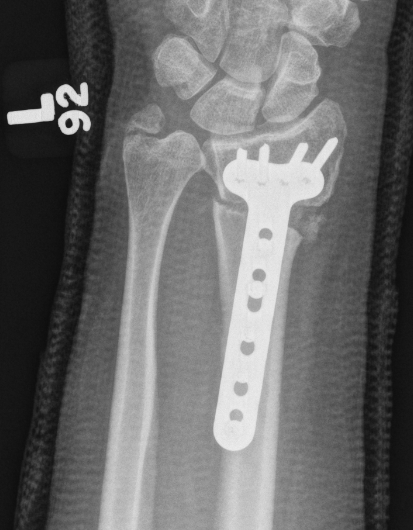

Volar versus dorsal radial osteotomy

- 28 patients undergoing osteotomy for radial malunion

- dorsal plate: increased complications including plate removal

- volar plate: increased undercorrection, difficulty with plate fitting

Volar opening wedge

Advantage

Volar approach and plate

Disadvantage

May require dorsal approach to bone graft

Technique

Vumedi volar osteotomy for distal radius fracture

Bed of FCR approach

- release brachioradialis

- protect structures with retractors

- perform osteotomy parallel to articular surface

- sufficient distal bone for screw fixation

- correct distal radius in two planes

- apply volar plate

- bone graft defect through radial aspect of wound

+/- dorsal approach to insert bone graft